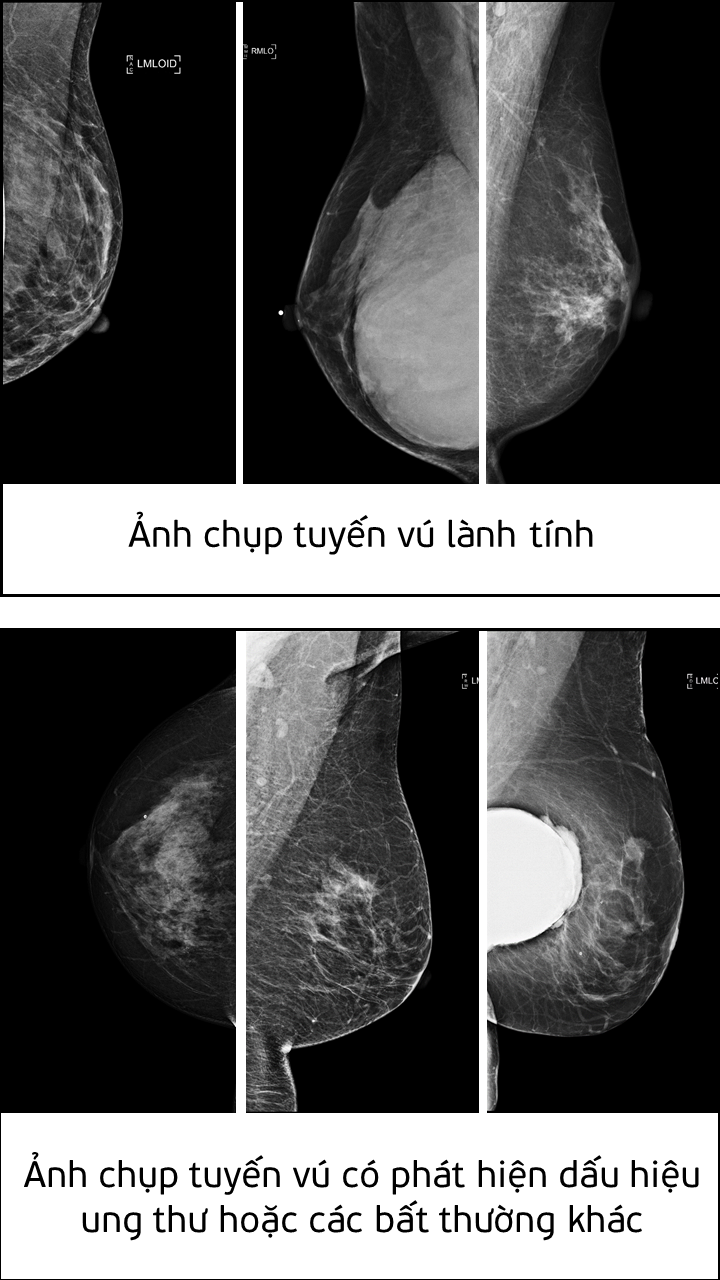

Giải pháp AI do Nguyễn Hồng Đăng phát triển có thể tự động nhận diện các dấu hiệu bệnh ung thư tuyến vú từ một vùng rất nhỏ trong nhũ ảnh. Giải pháp này có thể tích hợp vào hệ thống hỗ trợ phân tích (Computer-aided diagnosis - CADx systems) nhằm cải thiện tính chính xác trong việc chẩn đoán và khám chữa bệnh.

Theo đánh giá của Ban giám khảo, giải pháp của Nguyễn Hồng Đăng đã giải quyết được tình trạng mất cân bằng dữ liệu trong huấn luyện mô hình AI. Trong tệp dữ liệu mà cuộc thi đưa ra, tỷ lệ mẫu ung thư ác tính được gán nhãn chỉ chiếm khoảng 2% tổng số lượng mẫu, trong khi số lượng mẫu còn lại được gán nhãn lành tính hoặc bình thường chiếm 98%. Tình trạng mất cân bằng dữ liệu này có thể khiến cho trí tuệ nhân tạo dự đoán sai.

Theo Tổ chức Y tế Thế giới (WHO), ung thư vú là loại ung thư phổ biến nhất trên toàn cầu. Sàng lọc ung thư vú đã được chứng minh giảm tỷ lệ tử vong do ung thư lên đến 40%. Trong đó, công cụ trí tuệ nhân tạo có tiềm năng làm cho quá trình sàng lọc trở nên có giá trị và hiệu quả hơn.